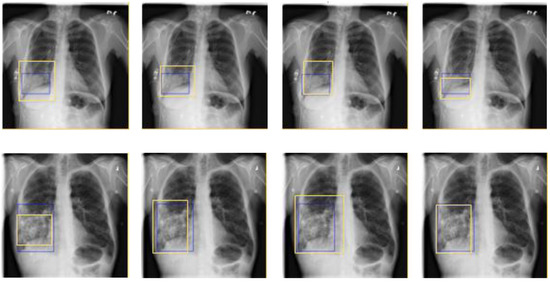

In the study, Yolov3 was improved by analyzing the advantages and disadvantages of the existing algorithms and combining the characteristics of the pneumonia dataset (see Figure 2). Small differences in the characteristics of lesion and non-lesion were believed to increase the difficulty of detecting lesion, but increasing the perception field of the algorithm so that it could use the global information in the image was expected to increase the recognition ability. Therefore, multi-branch dilated convolution [14,15] was added to Yolov3. In the Yolov3 object detection algorithm, multiple down-sampling operations result in the loss of semantic information and spatial information, making differences between lesion and non-lesion smaller in the feature space and improving the recognition ability of the algorithm. Although the fusion of low-level and high-level features can solve this problem to a certain extent, the use of attention mechanism to suppress the output of inaccurate semantic information in low-level features further improves the performance of the algorithm. The use of double K-means enables the algorithm to generate anchor boxes of different scales for different input images.

Figure 2.

Experimental data used in this study. The area within the blue box shows a pneumonia lesion. In images (a) and (b), there is no significant difference between pneumonia lesion and non-lesion. It can be seen from image (c) that the features of the left lesion and the right non-lesion are similar.